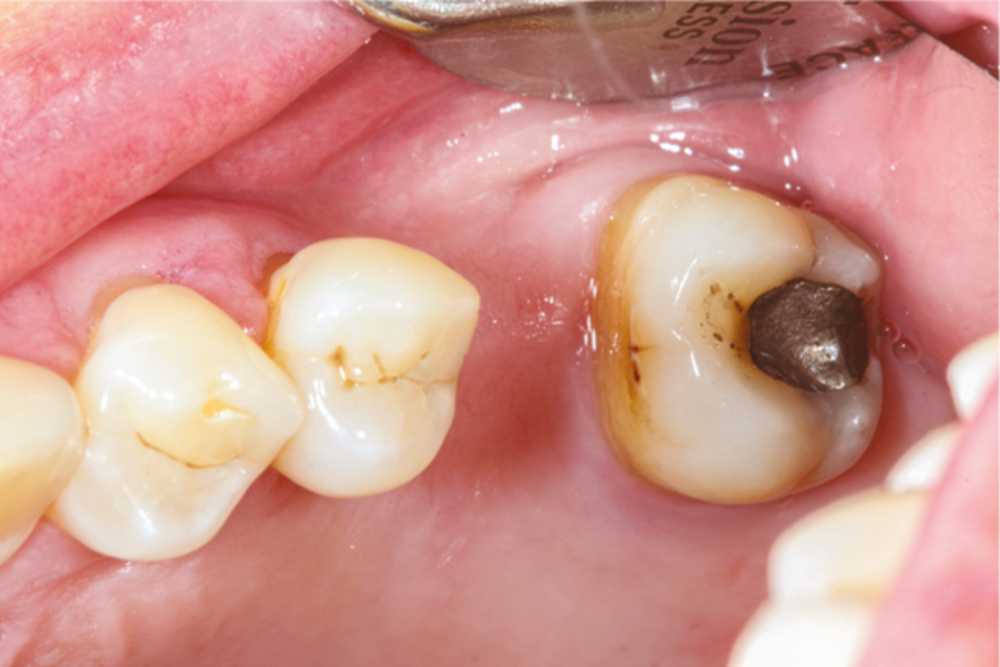

La version des dents distales peut aussi avoir des conséquences parodontales désastreuses : sur un parodonte réduit, une hypermobilité peut se développer, une poche parodontale peut aussi apparaître. Chez un patient parodontal, un « effet domino » est possible, des extractions non compensées diminueront donc le pronostic des dents restantes (fig. 7 à 9).

La répartition de la charge occlusale sur l’ensemble d’une arcade est aussi perturbée après une ou plusieurs extractions, ce qui peut occasionner des surcharges occlusales pour les dents restantes. Selon le délabrement coronaire de la dent [10], une fracture coronaire amélo-dentinaire ou corono-radiculaire peut intervenir sous cette surcharge occlusale et engager le pronostic de la dent concernée (fig. 14 à 17).